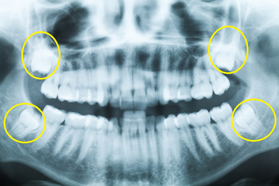

親知らずの種類

タイプ① 真っ直ぐ生えている親知らず

タイプ② 斜めに生えている親知らず

タイプ③ 水平埋伏の親知らず

歯茎の中で完全に横に生えてしまうタイプです。この親知らずを水平埋伏智歯と言います。

このタイプはほとんどが下顎のケースです。真横に生えているので抜歯の際は難易度が高く2~3つに砕いて分けて抜歯をします。